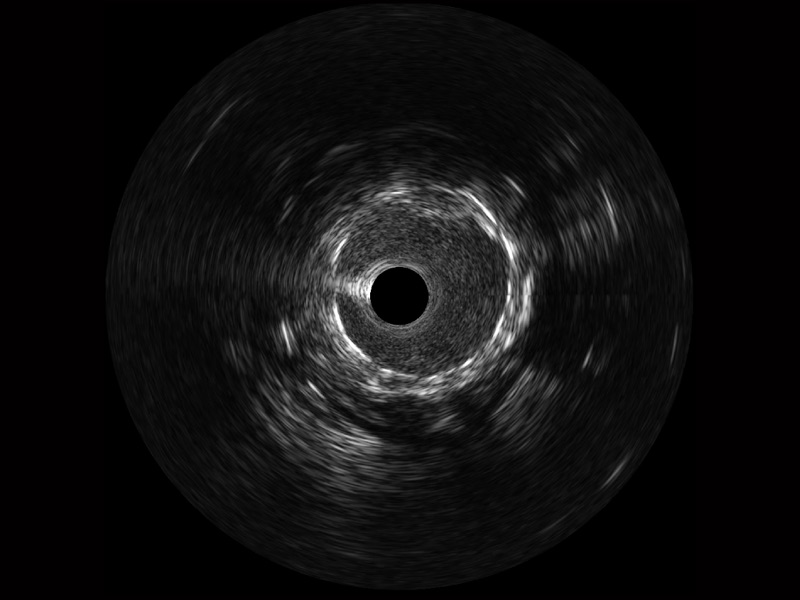

传统IVUS图像

对比传统IVUS导管成像,开立宽频IVUS图像的近场支架梁显影更细腻,远场中膜外血管仍清晰可辨,兼顾远中近,兼顾分辨力与穿透深度